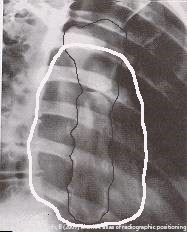

Why is RAO preferred for sternum imaging?

Places sternum over heart shadow, reducing lung/rib superimposition.

How much rotation is used for RAO sternum?

15–20° (15° hypersthenic, 20° asthenic).

Where is the CR directed for RAO sternum?

At T7, 2.5 cm left of midline.